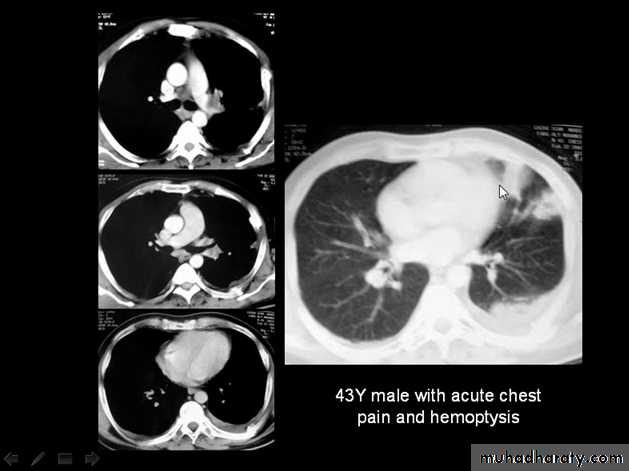

Massive pleural effusion with mediastinal shift to the left.

(A) Chest radiograph

(B) CT coronal reconstruction. A massive effusion displaces the mediastinum to the left. CT shows the important pleural effusion together with the enhanced atelectatic left lung.

Note also the depression of the right hemidiaphragm (arrows).